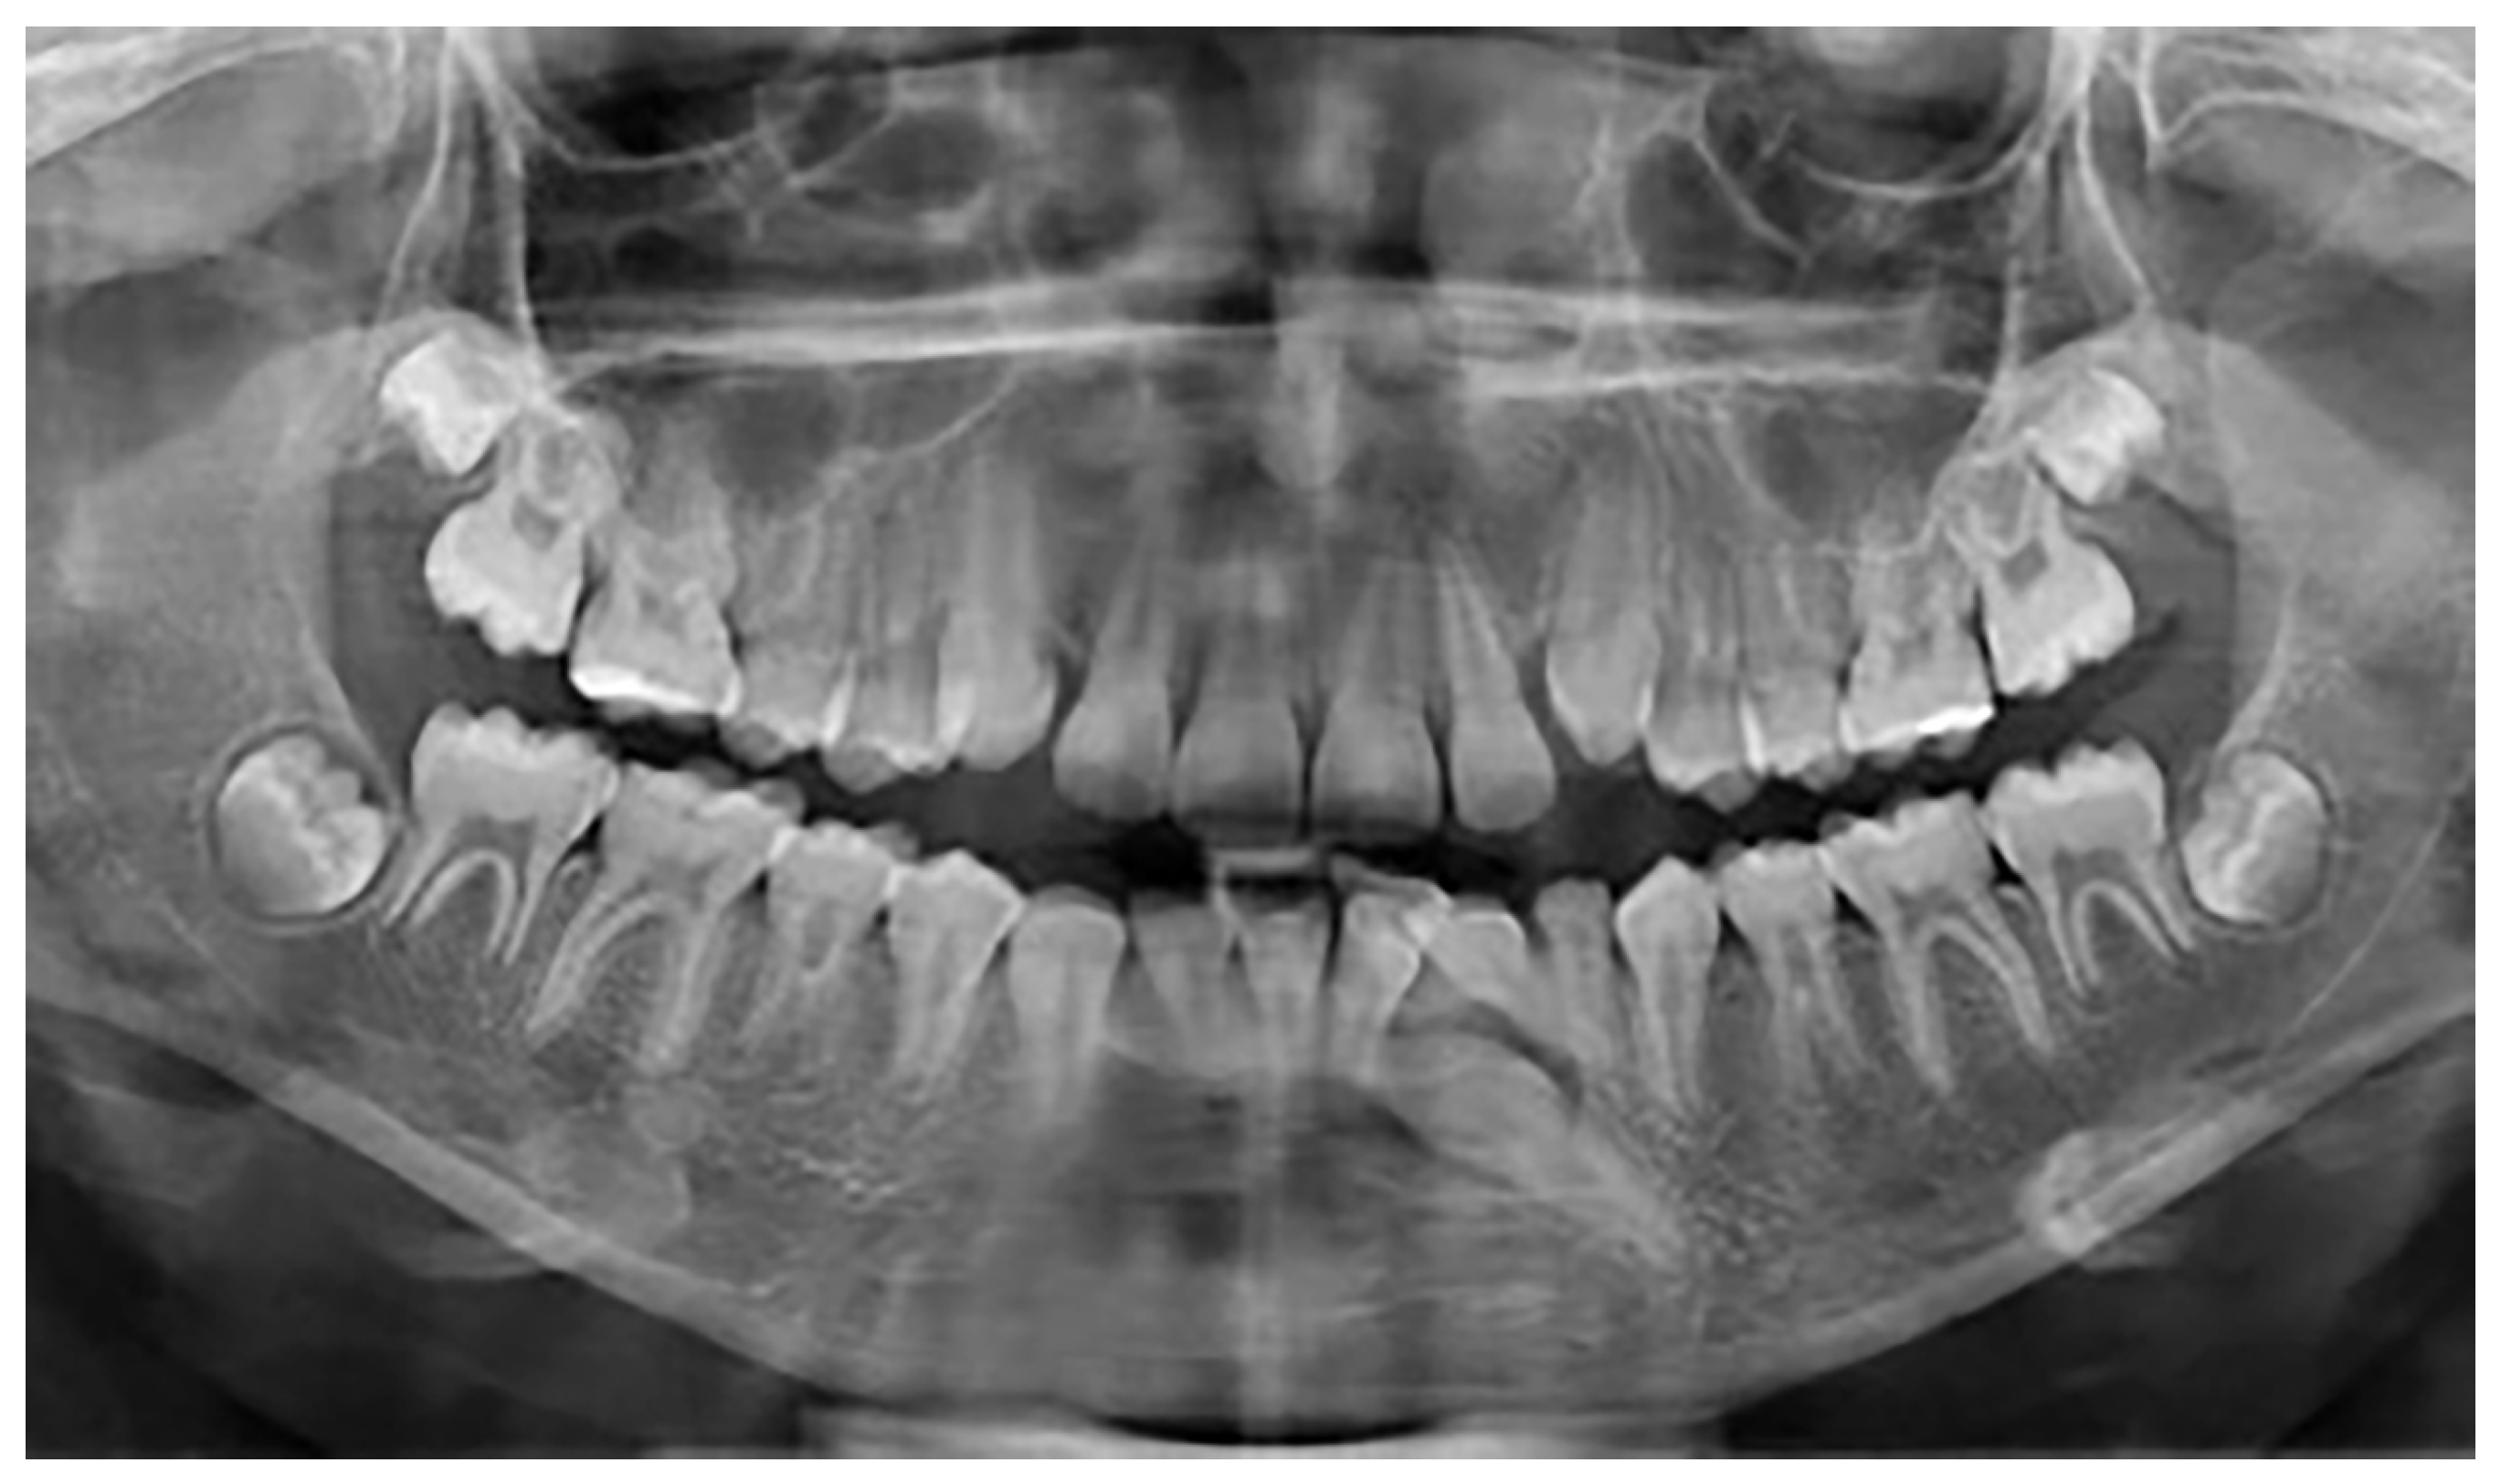

A total of 25 patients with mandibular canine impaction were found in Group A. Of these 25 patients, 14 were male and 11 were female. Canine impaction was bilateral in 12 patients and unilateral in 13 patients, with a total of 37 impacted permanent mandibular canine teeth. 21 impacted canines were found on the left side, and 16 canines on the right. 16 patients (64%) had retained deciduous canines at the time of diagnosis. In three cases, the impacted canines were transposed in the lateral incisor region. In one of the patients, there was a supernumerary tooth in the lateral incisor region, and the primary canine was still present in the dental arch (Figure 2). In one patient in whom the primary canine and primary lateral incisor were retained, impaction of both the lower permanent canine and lower permanent lateral incisor was noted. One patient was found to have complete impaction of all four canines. None of the patients had traumatic episodes, and none of them had systemic disorders. All the patients were asymptomatic.

Figure 2.

Mandibular impaction of left canine and presence of a supernumerary tooth.